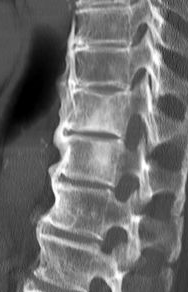

Diffuse Idiopathic Skelettal Hyperostosis ; Maladie de Forestier

DISH

- Ossification du ligament longitudinal antérieur

- Thoracique++

- Antérieur et coté droit (l’aorte empèche à gauche)

- Pointent horizontalement (spondylarthrite ankylosante = vertical)

- Peu d’arthrose interfacettaire ou de discopathies

- S’étend sur 4 niveaux au moins

- Risque de fractures transverses “Chalk Stick”